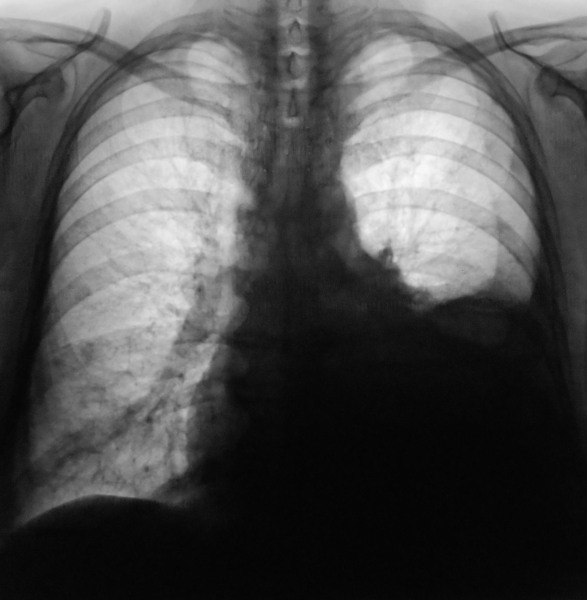

Рентгеновские снимки при врожденной эмфиземе легкого

Раздел: Визуальные уроки